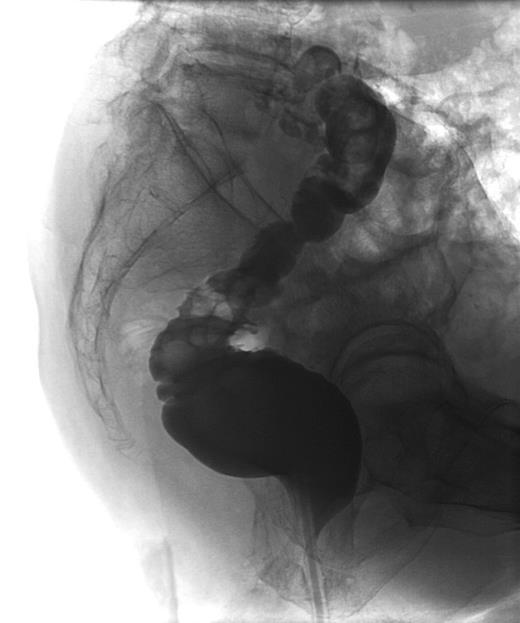

Three months after the initial operation, the patient presented with severe back pain radiating to both legs. The lower lumbar spine was highly tender on percussion, but the neurologic examination revealed only a slight loss of muscle strength in the big right toe. Vascular diseases of the lower extremities were excluded. The patient did not have fever at any time. Leucocytes were normal and CRP was moderately elevated to 42 mg/l. The MRI of the spine now revealed vertebral discitis without epidural abscess formation (Fig. 1). A barium enema excluded fistulas to the rectum (Fig. 2). Culture of CT-guided needle biopsy was positive with P. aeruginosa and antibiotic therapy with 6× 1 g Ceftazidime i.v. per day was started. The pain slowly improved and CRP values declined. After 20 days, the patient developed β-lactam-associated neutropenia. Therefore, treatment was changed to oral ciprofloxacin and continued for another 9 weeks. Pain was managed with fentanyl skin patch, paracetamol, metamizol and pregabalin. The patient fully recovered from the lower back pain. The loss of muscle strength in the big right toe persisted and was interpreted as stenosis of right S5 foramina due to infective destruction which did not require neurosurgical decompression.